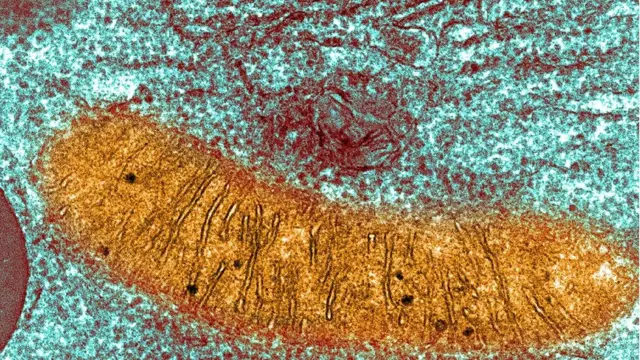

미토콘드리아는 세포 안에 있는 특별한 공간이다. 음식에서 나오는 에너지를 신체에 쓸 수 있는 형태로 변환한다. 하지만 미토콘드리아에 질병을 일으키는 결함이 있으면, 이 기능을 수행할 수 없다. 우리는 어머니에게 미토콘드리아를 물려받기 때문에, 여성이 결함이 있는 미토콘드리아를 가졌다면 그것이 자녀에게도 이어질 수 있다.